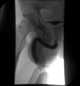

Isolated symphyseal diastasis

Wide pubic symphysis